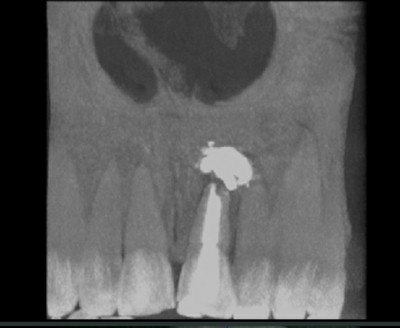

если у вас вторые зубы, как на картинке.то это нормально. двойки обычно короче центральных зубов. после снятия брекетов- наращивать или нет решать только вам.хотите чтобы были вровень, вам не откажут

Иллюстрация к комментарию